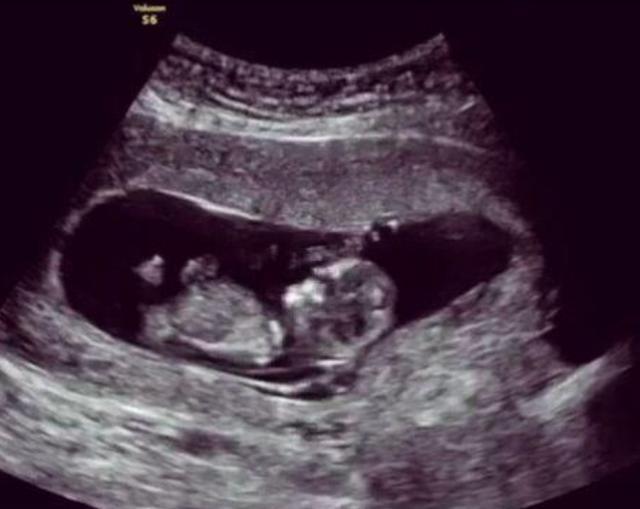

案例小吕和妻子结婚后日子就过得非常的和美,在别人的眼里他们就是模范夫妻的典范,在结婚后不久妻子就怀孕了,小吕也是非常的激动和开心,并且在日常生活中对于怀孕的妻子更是无微不至的照顾着,每一次妻子做产检,小吕都要亲自去陪伴。这天小吕又要陪着妻子去医院产检,头天晚上俩人还在一起数着胎动畅想着孩子的模样和未来,结果到了医院,门诊护士在给妻子听胎动的时候神情变得非常的紧张,还让旁边的护士赶紧去叫来了主治医生,然后就推着妻子进入了手术室,小吕知道情况不妙,可能是妻子和孩子出问题的。

小吕一直在产科的手术之外焦急的等待着,过了很长时间,妻子的主治医生终于出来了,小吕马上上前询问妻子和孩子的情况“医生,我的妻子和孩子怎么了?她们怎么样了?”医生回答说“现在胎儿的状态不是很好,需要引产,你赶紧准备一下并且办理下住院手续吧。”小吕当时就懵了,妻子再有2周就是预产期了,怎么却突然要引产了呢?

分析医生做引产的时候,发现胎儿并没有出现脐带绕颈的情况,并且胎位什么的也很正常,但是为什么胎儿就没有了心跳呢?在做完手术后,妻子被推回了病房,夫妻俩面面相觑都是一脸愁容,家里还放着一堆为孩子准备的东西,但是现在孩子却胎死腹中了,这样的事情换了谁肯定都是很难接受得了的。但是没有办法,就算是现在医疗水平如此高,对于“胎死腹中”的事情依然是没有任何办法解决不了,甚至都没有答案,一个新的生命就这么戛然而止了。